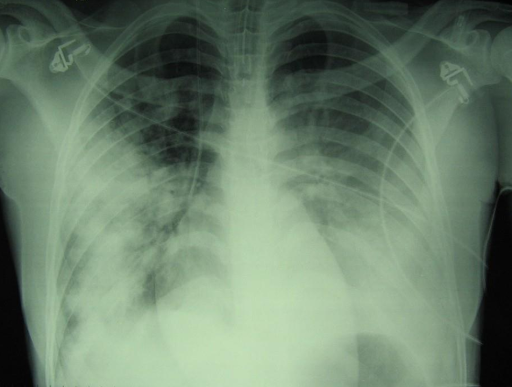

ARDS_3.png

Die nachfolgende Thorax-CT-Untersuchung zeigt eine teilweise radiologische Besserung nach einer gezielten nicht-konventionellen Therapie.